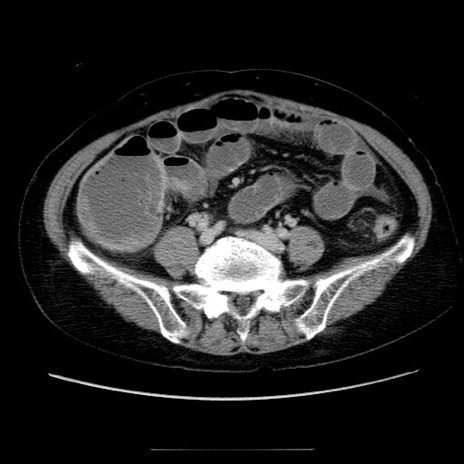

【症例】70歳代女性

【主訴】お腹が張る

【現病歴】1週間くらい前から腹部膨満の自覚あり。昨日夜から増悪したため、本日救急外来受診。

【身体所見】意識清明、BT 36.5℃、BP 165/106mmHg、HR 80bpm、SpO2 98%、腹部:膨満、軟、自発痛・圧痛なし、触診にて不快感あり、腸蠕動音:減弱

【データ】WBC 12600、CRP 1.04